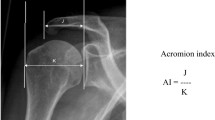

The influence of acromial anatomy on the genesis of atraumatic rotator cuff tears has long been debated [1, 3, 6, 8, 14, 21, 30]. Morphologic features of the acromium, as a potential etiology, have been shown to be unreliable [13], and there is increasing evidence that cuff disease is linked primarily to an age-related degenerative process [19, 22]. Theories linking acromial characteristics to rotator cuff disease have fueled the debate regarding the role of extrinsic (mechanical impingement) versus intrinsic (biologic degeneration) factors in the development of rotator cuff tears [3, 19, 22, 30]. Other acromial morphologic measurements such as acromial index and the critical shoulder angle (CSA) (Fig. 1) have been proposed to be associated with the etiology of rotator cuff disease [2, 7, 10, 15, 26]. The CSA is a measurement that combines lateral acromial offset and glenoid inclination [2, 5, 7, 15, 24, 26, 31]. A more-lateral acromial offset creates a more-lateral deltoid origin and, in theory, results in greater shear and lesser compressive vector of the deltoid across the glenohumeral joint [10]. In some studies, a larger acromial index, which is a measure of lateral acromial offset [2, 26], has been reported to be associated with rotator cuff disease [2, 3, 26, 30], whereas another study showed no such relationship [13]. Glenoid inclination also may play a role in the development of rotator cuff disease [7, 15]. Superior glenoid inclination increases shear forces and decreases compression forces across the glenohumeral joint and may encourage proximal humeral migration and increase loads placed on the articular margin of the supraspinatus to resist the deltoid [5, 7, 15, 24, 31].

Shoulder radiographs were obtained at baseline and annually using a standardized protocol by specifically trained technicians, as previously described [20]. These radiographs then were evaluated by two independent observers (PNC, DS) with our digital radiography software suite (PACS; General Electric, Fairfield, CT, USA) using a standardized protocol. The observers who performed the radiographic measurements were blinded to ultrasonographic and clinical findings for each subject. Only true AP radiographs were evaluated. Given that the accuracy of the CSA is influenced by subtle variances in scapular position [32], strict criteria were used to include only the highest quality radiographs. Specifically, we used the Suter-Henninger grading scale [32]. This scale grades whether the Grashey view radiograph obtained is perfectly orthogonal to the glenoid mediolaterally (type A) or not (types B, C, and D) and whether it is perfectly orthogonal to the glenoid superoinferiorly (type 1) or not (types 2 and 3) (Fig. 3). A previous study showed that excluding radiographs with types A2/3, B1/2/3, C2/3, and D1/2/3, improves CSA accuracy such that 89% of measurements will be within less than 2° of accuracy (Fig. 3) [32]. Starting with the radiograph obtained at the time of study enrollment, each yearly longitudinal radiograph was graded until an appropriate-quality radiograph, as defined by the Suter-Henninger scale, was obtained. If no adequate radiograph could be located, then the patient was excluded from the study. The CSA then was measured digitally as the angle between a line from the inferior-most subchondral glenoid to the lateral acromial edge and a line from the superior-most subchondral glenoid to the inferior-most subchondral glenoid, as previously described (Fig. 4) [5, 26, 31, 32]. Previous studies showed that the CSA can be measured reliably on plain radiographs and that it is not necessary to obtain a CT scan [5] or MRI [31] to evaluate this angle.